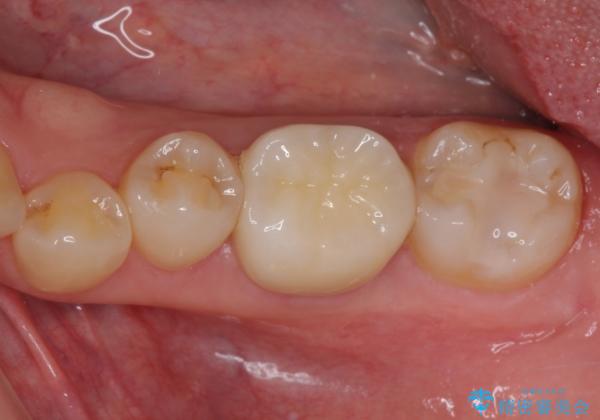

後日状態を確認したところ、残された神経に異常がなかったため、フルジルコニアクラウンにて補綴治療を行いました。